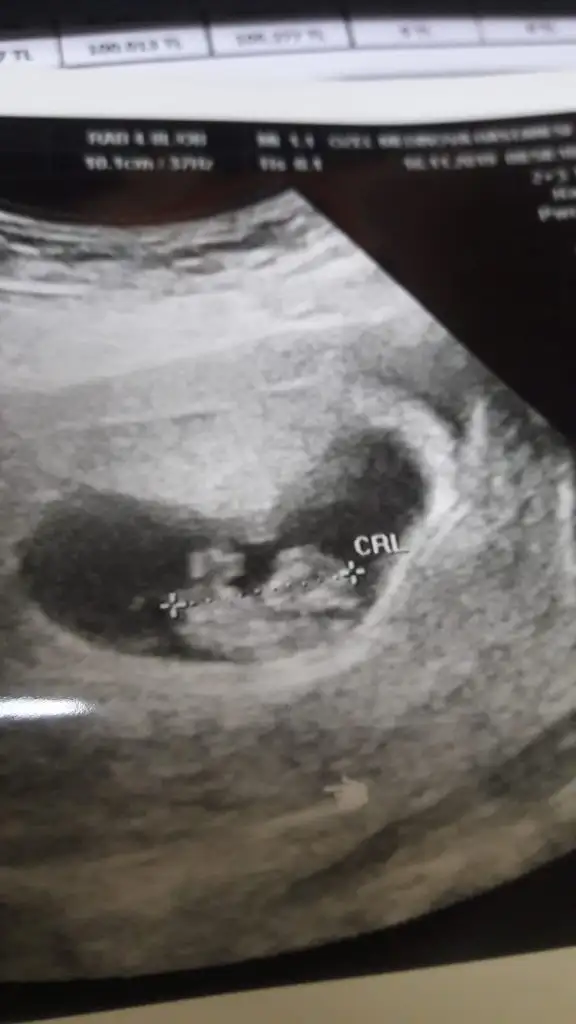

dr soylemeden siz gorun genital nub teorisi ( bebegin cinsiyeti)

Kızlar yorum istiyorum doktor daha küçük dedi 12 haftada ☺️☺️